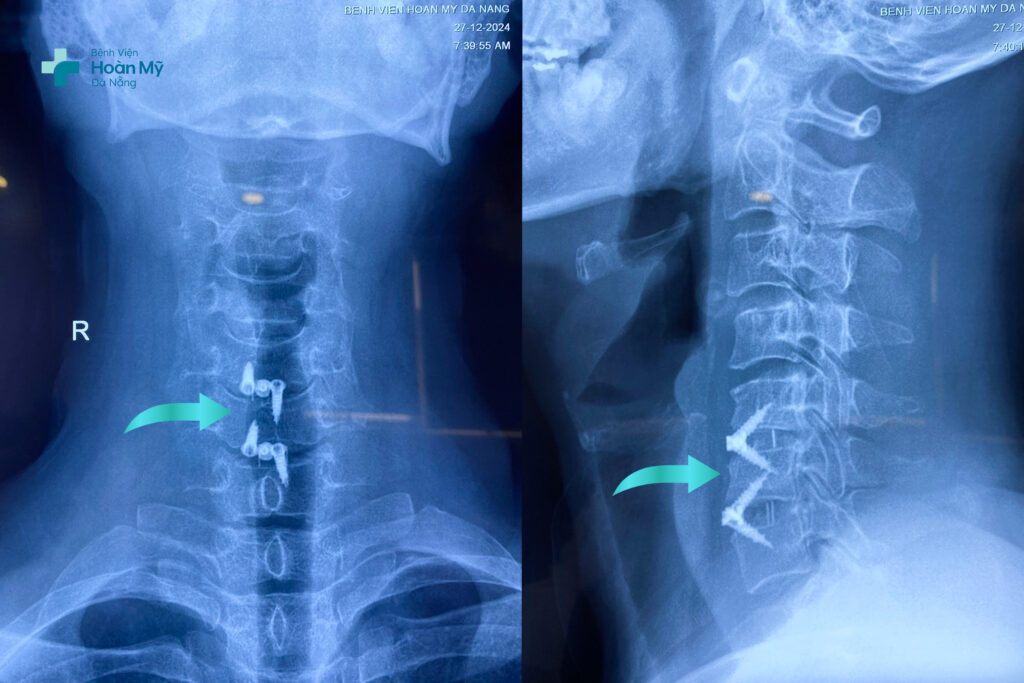

X-quang về vết hàn xương cột sống bằng phương pháp ACDF trên người bệnh

ACDF là phẫu thuật có độ khó cao và tinh tế đòi hỏi phẫu thuật viên phải có kinh nghiệm chuyên môn sâu, trang thiết bị phòng mổ hiện đại như: kính vi phẫu; màn hình tăng sáng trong phẫu thuật; máy mài cao tốc; hệ thống phòng mổ đạt chuẩn quốc tế giúp phẫu thuật viên quan sát tốt phẫu trường, lấy đĩa đệm thoát vị chèn ép rễ thần kinh và hàn xương cột sống cổ chính xác, kiểm soát tốt các tai biến.